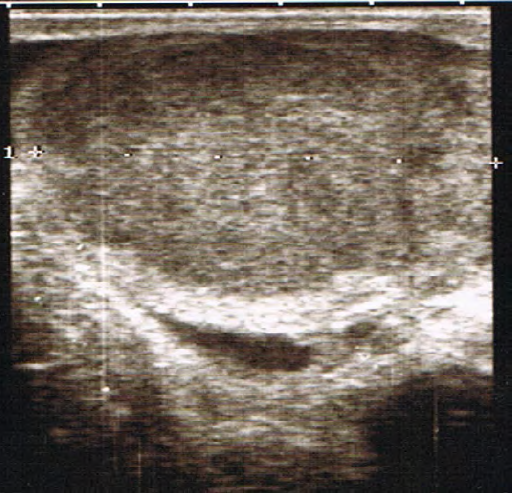

Presentamos el caso clínico de un hombre de 33 años de edad que consulta por aumento progresivo de tamaño del testículo derecho de tres meses de evolución. No refiere dolor ni sintomatología urinaria. No presenta alergias ni patologías de interés. Refiere un desarrollo psicomotriz normal sin antecedentes de criptorquidia ni hidrocele durante la infancia. Niega consumo de alcohol, tabaco u otras drogas. A la exploración física, se aprecia un aumento difuso del tamaño y consistencia del testículo derecho con transluminiscencia negativa. El testículo izquierdo es normal. No se palpan adenopatías inguinales ni en el resto de su anatomía. No presenta ginecomastia, visceromegalias ni irritación peritoneal. Decidimos realizar una ecografía testicular en Atención Primaria, apreciando una alteración de la ecoestructura de forma difusa sin presencia de quistes ni calcificaciones (figura 1). Solicitamos analítica completa con marcadores tumorales, radiografía de tórax y remitimos con carácter preferente a la consulta de Urología. Tanto el hemograma como la bioquímica básica fueron rigurosamente normales, así como la AFP, BetaHCG y LDH. La radiografía de tórax fue igualmente normal. Dado el dilatado tiempo de espera para la consulta de Urología, decidimos remitir al paciente a la Urgencia Hospitalaria con el estudio completo realizado en Atención Primaria. Se realizó una ecografía testicular reglada que confirma: “Testículo derecho aumentado de tamaño con alteración difusa de la ecogenicidad, sin calcificaciones, presenta aumento difuso de la vascularización. Proceso inflamatorio de tipo orquitis derecha, no obstante, dado el tiempo de evolución no se descarta proceso neoplásico” (figura 2). Ingresa en Urología y se realiza orquiectomía radical inguinal derecha. Anatomía patológica informa: “Seminoma clásico de diámetro mayor de 8 cm, sin evidencia de infiltración de la túnica albugínea. Restos de parénquima testicular con focos de tumor germinal intratubular. Epidídimo y borde de resección del cordón espermático sin evidencia de malignidad”. Ante dichos hallazgos, se realiza Tomografía Computerizada (TC) abdominopélvico para su estadificación: “No se observan adenopatías mediastínicas, hiliares ni axilares de tamaño significativo. Adenopatía paracardiaca derecha de 6 mm y micronódulo de 4 mm en LM. No se observan adenopatías retroperitoneales ni pelvianas de aspecto patológico. Se observan hallazgos compatibles con paniculitis mesentérica y adenopatías inguinales bilaterales de aspecto reactivo secundarias a la cirugía. Resto de estudio sin hallazgos”. Fue remitido a Oncología con el diagnóstico de seminoma puro estadio I. Dado que más del 80 % de los casos nunca recaen, en correlación con la Guía de la Asociación Europea de Urología, se decide realizar vigilancia sin necesidad de tratamiento adyuvante. Sin embargo, el riesgo pequeño, pero clínicamente significativo de recidiva, respalda la necesidad de vigilancia a largo plazo2 e iniciar radioterapia o quimioterapia basada en cisplatino, de rescate. Como las recidivas ocurren principalmente en los primeros 2 años, se recomienda el seguimiento mediante TC cada 3 meses el primer año, cada 4 meses el segundo y cada 6 y 12 meses en los años siguientes3. Nuestro paciente lleva más de 3 años de seguimiento, sin datos de recaída. Los hallazgos inespecíficos presentes en el primer TC han desaparecido y los marcadores tumorales se mantienen negativos hasta la actualidad.

La ecografía sirve para confirmar la presencia de una masa testicular y para explorar el testículo contralateral. Su sensibilidad en la detección de un tumor testicular es prácticamente del 100 % y desempeña un papel importante a la hora de determinar si la masa es intra o extratesticular. Se suelen presentar como una o varias masas hipoecoicas (seminoma) o hiperecoicas con microcalcificaciones4. Es una prueba económica y debe realizarse incluso si hay un tumor clínicamente evidente; así como en varones jóvenes que presentan masas viscerales o retroperitoneales, elevación de los marcadores tumorales séricos o en hombres con problemas de fertilidad; presenten o no, masa escrotal palpable.